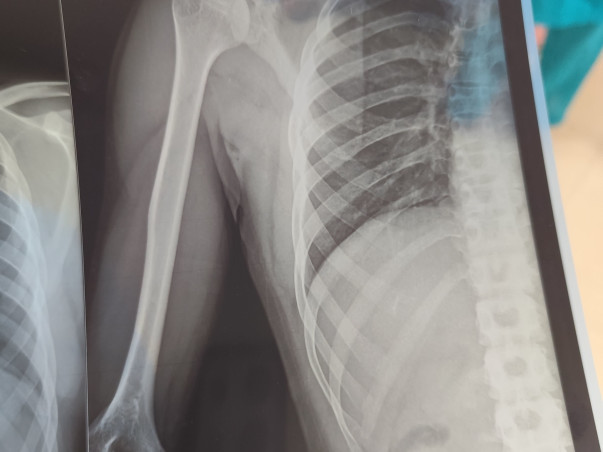

Recently, Palash met with a serious accident, suffering multiple fractures (polytrauma). He is currently receiving medical treatment at Gauhati Medical College Hospital, though he has not yet been admitted.